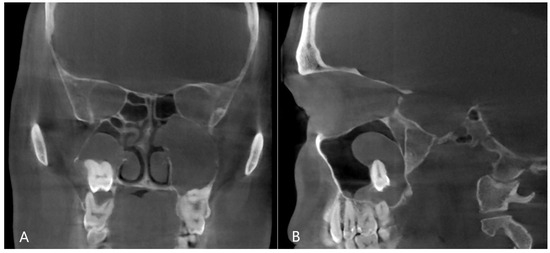

Figure 4. CBCT image of odontogenic cyst with calcified capsule, highly impacted upper wisdom tooth in the right maxillary sinus. Left chronic odontogenic sinusitis caused by impacted left upper wisdom. ((A): coronal, (B): sagittal view).